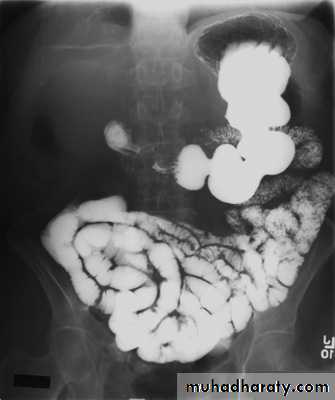

The standard contrast examination is barium follow-through (that involves drinking 200-300 ml of barium then taking films at regular intervals until the barium reaches the colon). It may take 2-3 hoursNormal barium follow-through

The barium forms a continuous column defining the diameter of bowel (< 25 mm). Transverse mucosal folds appear as lucent filling defects of about 2-3 mm in width. When the SB is contracted, their appearance is described as feathery. The folds are largest & numerous in jejunum & tend to disappear in the lower parts of ileum.enteroclysis

A long segment of narrowed ileum (string sign) is present with proximal ileal dilation& caecal contraction

TI

caecum